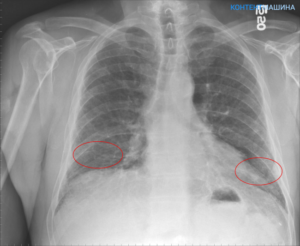

Для диагностики фиброза также используют рентгенологические методы:

- рентгенограмма необходима для визуализации легочного рисунка;

- компьютерная томография дает возможность увидеть очаговые, периферийные, субплевральные, сетевидные затемнения органа;

- эхокардиограмма нужна для подтверждения легочной гипертензии.